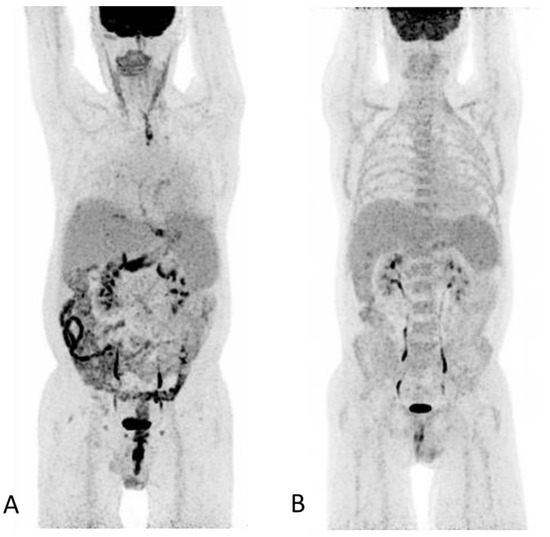

Axial CT image shows circumferential small bowel wall thickening (>3 mm) with trilaminar mural stratification in the small-bowel (circle and magnified image) with serosal enhancement (red arrow), low intramural attenuation (yellow arrow) and mucosal enhancement (white arrow) [2,13]. Low intramural attenuation can represent edema, inflammatory infiltrate or fat [13]. Stranding of the mesenteric fat is often observed in GIT-GVHD [2,6] (arrows). Mural stratification is a non-specific sign of bowel inflammation and has been shown to correlate with clinically active disease as opposed of a more homogenously enhancement due to fibrosis [14,15]. In this patient, three different patterns of mural stratification and mural enhancement were present in separate segments (Figure 2 and Figure 3).